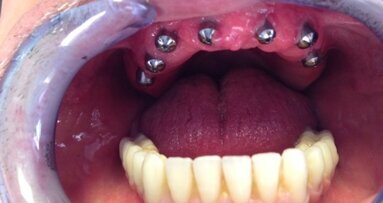

Mężczyzna, l. 34 zgłosił się do kliniki z powodu braków międzyzębowych oraz ruchomości zębów przednich III0 (Ryc. 1 i 2). Po przeprowadzeniu wywiadu, badania i etapu diagnostycznego zaproponowano plan leczenia, który po zaakceptowaniu przez pacjenta zrealizowano. Terapia obejmowała: leczenie kanałowe zęba 13 wraz ze wzmocnieniem filaru wkładem koronowo-korzeniowym i preparacją pod koronę protetyczną, ekstrakcję zębów 12, 11, 21, 22 i 23 wraz z zaopatrzeniem natychmiastową protezą ruchomą (Ryc. 3).

Kolejny etap, po 6-miesięcznym okresie gojenia obejmował procedury chirurgiczne polecające na ekstrakcji zębów 15 i 14, implantacji natychmiastowej w pozycji 15 oraz implantacji w pozycjach zębów 11, 21, 23, 24 wraz z augmentacją deficytów kostnych materiałem kościozastępczym i błoną zaporową (Ryc. 4). W celu rejestracji położenia płaszczyzny OA w stosunku do osi zawiasowej stawów skroniowo-żuchwowych użyto arbitralny łuk twarzowy. Do ustalenia relacji centralnej (RC) wykorzystano wewnątrzustną rejestrację zwarcia funkcjagrafem wg Kleinrok, który razem z łukiem twarzowym i artykulatorem stał się Technicznym Zespołem Modelowych (Majewski).

W celu poprawy końcowego efektu estetycznego, po odsłonięciu implantów wykonano tymczasowy most kompozytowy, aby ukształtować rzekome brodawki dziąsłowe (Ryc. 5 i 6). Jako uzupełnienie docelowe wykonano 2, dzielone w linii pośrodkowej mosty metaloceramiczne cementowane na łącznikach standardowych (Ryc. 7).